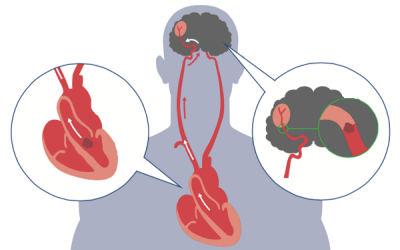

Tăng huyết áp có thể gây ra nhiều bệnh nguy hiểm như tim mạch, đột quỵ, võng mạc tăng huyết áp… Tuy nhiên, nhiều người vẫn chưa hiểu rõ về căn bệnh này và thường có những suy nghĩ...